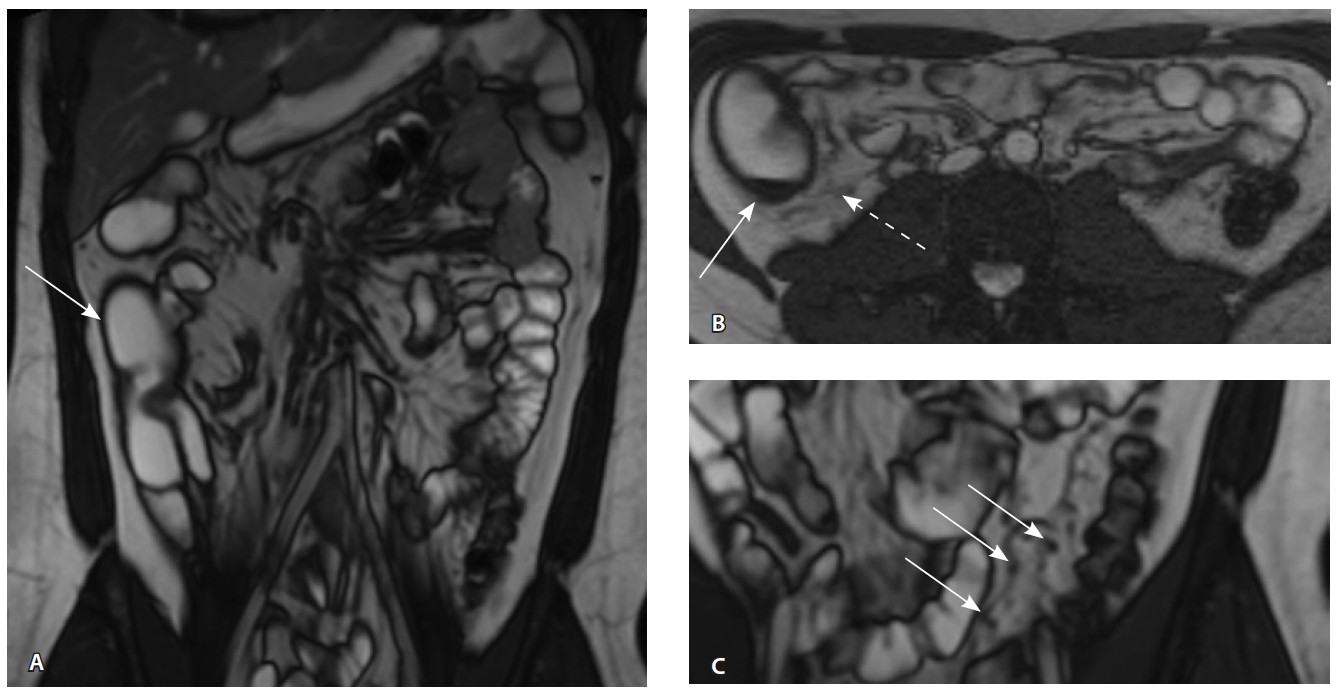

Назначена ГИБТ адалимумабом (препарат Хумира) по стандартной схеме 160 мг п/к (неделя 0), 80 мг п/к (неделя 2) с последующим плановым поддерживающим режимом 40 мг п/к каждые 2 недели. Через 9 месяцев установлена эндоскопическая ремиссия, однако сохранялась концентрация фекального кальпротектина более 2000 мкг/г. Через год жалобы возобновились, тогда же впервые была выявлена задняя анальная трещина. Выполнена магнитно-резонансная энтерография, обнаружены воспалительные изменения, характерные для БК (рис. 2 и 3).

Рис. 3. Магнитно-резонансная энтерография, Т1-взвешенное изображение после внутривенного контрастного усиления (гадобутрол, 5 мл): А – фронтальная проекция, Б – аксиальная проекция. Наблюдается выраженное усиление интенсивности сигнала от восходящего отдела ободочной кишки (стрелка), усиление сигнала от окружающей клетчатки (пунктирная стрелка)